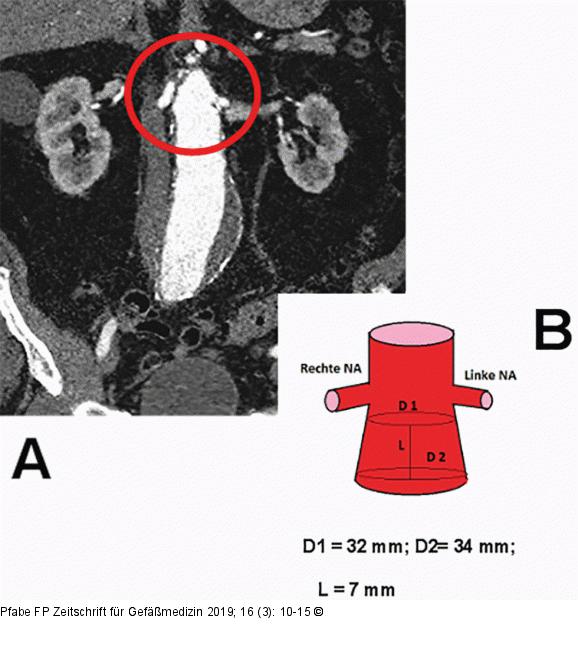

Abbildung 4: Infrarenales Aortenaneurysma Infrarenales Aortenaneurysma. (A): Kontrastmittelverstärkte CT-Angiographie (koronare Schnittebene), Visualisierung der „hostile neck“-Konfiguration des Aneurysmahalses (roter Pfeil); (B): Messprotokoll der proximalen Landungszone, Länge (7 mm) und Querdurchmesser entsprechen einer „hostile neck“-Anatomie und „conical neck“-Morphologie. |